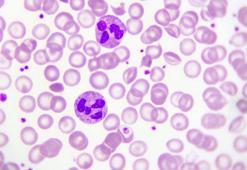

Bazofil nedir? Bazofil oranı kaç olmalı? Bazofil yüksekliği veya düşüklüğünün nedeni nedir?

İnsan vücut yapısında oldukça yüksek oranda hücre bulunur. Kan yoluyla taşınan bu hücreler arasında bazofil hücresi de yer almaktadır. Belirli bir referans değer aralığı arasında bulunması gereken bazofil değeri, kan testi üzerinden ölçülür. Düşüklüğü ya da yüksekliğine bağlı olarak belli başlı bazı hastalık risk faktörleri oluşturabilmektedir. Peki, Bazofil nedir? Bazofil oranı kaç olmalı? Bazofil yüksekliği veya düşüklüğünün nedeni nedir? İşte detaylar.13 Mayıs 2020 Çarşamba

Nötrofil (NEU) nedir? Nötrofil yüksekliği veya düşüklüğünün sebebi nedir? Nötrofil yüzdesi nedir, kaç olmalı?

Nötrofiller (NEU), vücudu enfeksiyonlardan koruyan bir tür beyaz kan hücreleridir. Bakteriyel bir enfeksiyon geçirildiğinde ortaya çıkan ilk hücrelerdir. Vücuttaki zararlı olan bakteri ve virüsleri bulur ve onları yok etmek için savaşmaya başlarlar. Vücudunuz için önemli olan bu hücreleri iyi tanıyıp, ona göre önleminizi alabilirsiniz. Nötrofil yüzdesi kaç olmalı, yüksekliği ve düşüklüğü ne demek sizler için derledik.10 Mayıs 2020 Pazar